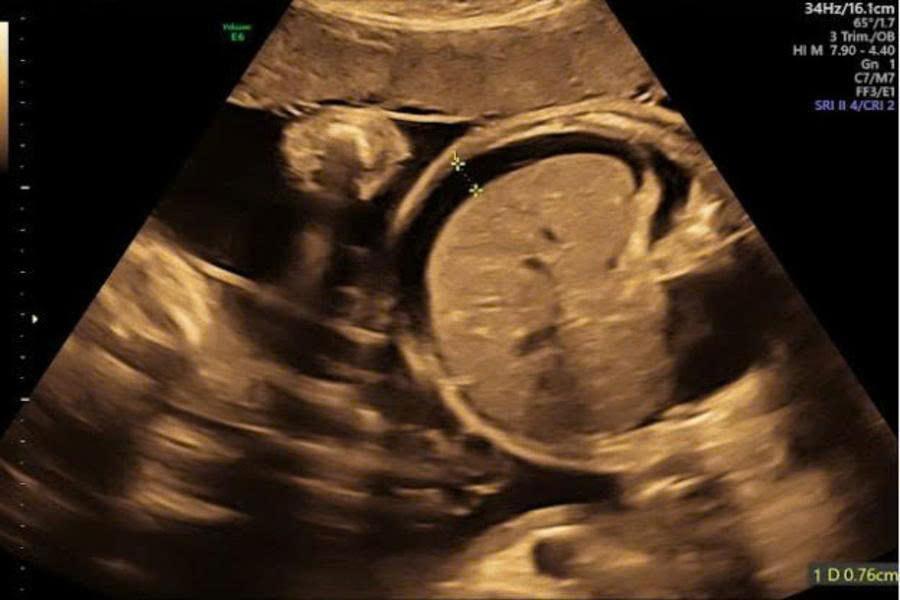

Chọc hút dịch màng bụng thai nhi dưới siêu âm (fetal paracentesis) là một thủ thuật xâm lấn có kiểm soát, trong đó bác sĩ sử dụng kim chuyên dụng đưa qua thành bụng mẹ, vào tử cung và tiếp cận khoang bụng của thai nhi để hút bỏ lượng dịch dư thừa. Toàn bộ quá trình được thực hiện dưới hướng dẫn trực tiếp của siêu âm, giúp đảm bảo độ chính xác cao và hạn chế tối đa nguy cơ tổn thương thai, bánh rau hay dây rốn.

Thủ thuật này thường được chỉ định trong các trường hợp tràn dịch màng bụng thai nhi (fetal ascites) – tình trạng dịch tích tụ bất thường quanh gan, ruột, dạ dày. Đây có thể là biểu hiện đơn độc hoặc nằm trong bối cảnh phù thai toàn thân (hydrops fetalis) khi dịch xuất hiện đồng thời ở nhiều khoang như màng phổi, màng tim.

Trong quá trình can thiệp, bác sĩ sử dụng kim chuyên dụng mảnh (20–22G), tiếp cận khoang phúc mạc thai nhi dưới sự theo dõi liên tục của siêu âm. Dịch được hút với mục đích giảm áp lực hoặc lấy mẫu xét nghiệm. Sau thủ thuật, thai nhi được siêu âm đánh giá nhịp tim, lượng dịch còn lại và phát hiện sớm các biến chứng.